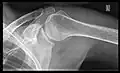

Shoulders

_X-ray_of_a_normal_shoulder.jpg)

These include:

- AP-projection 40° posterior oblique after Grashey

The body has to be rotated about 30 to 45 degrees towards the shoulder to be imaged, and the standing or sitting patient lets the arm hang. This method reveals the joint gap and the vertical alignment towards the socket.[17]

- Transaxillary projection

The arm should be abducted 80 to 100 degrees. This method reveals:[17]

- The horizontal alignment of the humerus head in respect to the socket, and the lateral clavicle in respect to the acromion.

- Lesions of the anterior and posterior socket border or of the tuberculum minus.

- The eventual non-closure of the acromial apophysis.

- The coraco-humeral interval

- Y-projection

The lateral contour of the shoulder should be positioned in front of the film in a way that the longitudinal axis of the scapula continues parallel to the path of the rays. This method reveals:[17]

- The horizontal centralization of the humerus head and socket.

- The osseous margins of the coraco-acromial arch and hence the supraspinatus outlet canal.

- The shape of the acromion

This projection has a low tolerance for errors and accordingly needs proper execution.[17] The Y-projection can be traced back to Wijnblath's 1933 published cavitas-en-face projection.[18]

In the UK, the standard projections of the shoulder are AP and Lateral Scapula or Axillary Projection.[15]